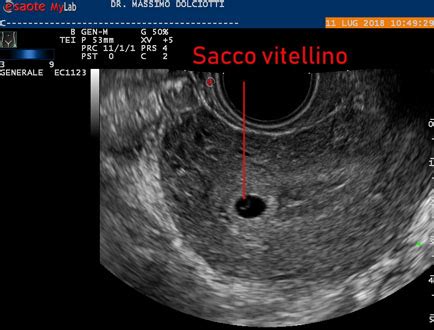

Il Sacco Vitellino: La Prima Fonte di Nutrizione

Nelle primissime settimane, all'interno della camera gestazionale, è visibile il “sacco vitellino” prima ancora dell’embrione. Questa struttura, descritta come una sorta di paracadute a cui è attaccato l’embrione stesso, gioca un ruolo cruciale nelle primissime fasi dello sviluppo. La sua funzione principale è quella di fornire alle prime cellule i nutrienti essenziali, sostenendo la crescita e lo sviluppo embrionale prima che la placenta sia completamente formata e funzionale. La sua presenza e le sue caratteristiche sono, pertanto, indicatori importanti dello sviluppo precoce.